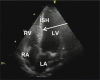

Hypertrophic cardiomyopathy (HCM) is the most common inherited cardiac disease. The disease is characterized by marked variability in morphological expression and natural history, ranging from asymptomatic to heart failure or sudden cardiac death. Left ventricular hypertrophy and abnormal ventricular configuration result in dynamic left ventricular outflow obstruction in most patients. The goal of pharmacological therapy in HCM is to alleviate the symptoms, and it includes pharmacotherapies and septal reduction therapies. In this review, we summarize the relevant clinical issues and treatment options of HCM.